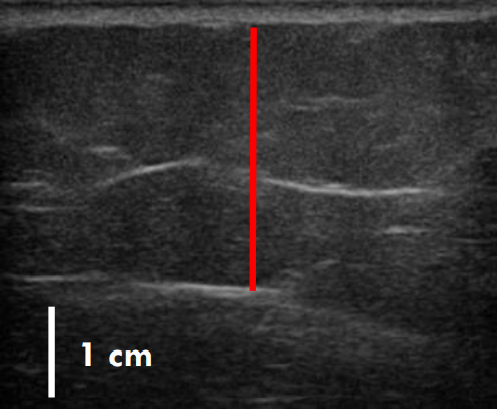

트루스컬프iD 시술 전 / 12주 후 초음파 사진 비교

트루스컬프 아이디 시술 전 / 12주 후 (초음파)

트루스컬프 아이디 시술 전, 12주 후 초음파를 비교한 사진입니다.

시술 전과 비교했을 때 약 36% 정도 지방이 감소한 효과를 볼 수 있는데요. 실제 운동으로 뱃살을 빼 본 분들이라면 아시겠지만 운동이나 식이요법으로 이 정도의 지방 감소 효과를 보려면 상당한 노력과 체계적인 관리를 필요로 하지요.